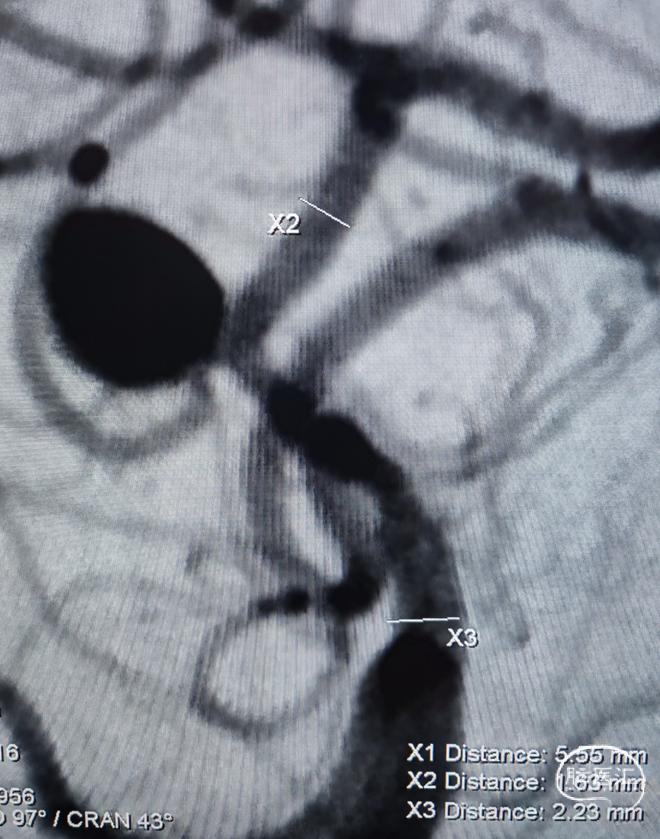

一般项目:患者女 年龄:71岁;

因“检查发现脑内动脉瘤10天”入院;

外院造影检查发现右侧大脑中动脉M1段动脉瘤、右侧颈内动脉眼动脉段动脉瘤。

⇨FD结合弹簧圈动脉瘤栓塞术

Lattice 2.6x18

1、定位精准、原位释放:首个显影标记对准支架落点:放在定位点附近即可原位释放, 简化操作、免支架拖拽、减少血管损伤和支架扭结;全程多个显影标记可视化支架释放进程:完全掌握手术操作,安全性高;